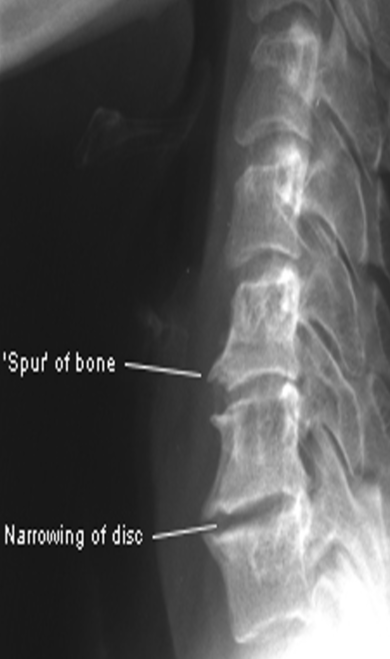

Rad - Disc Herniation

narrowed disc space

osteophytes

best seen in MRI (required for diagnosis), CT is also valued when MRI is contraindicated